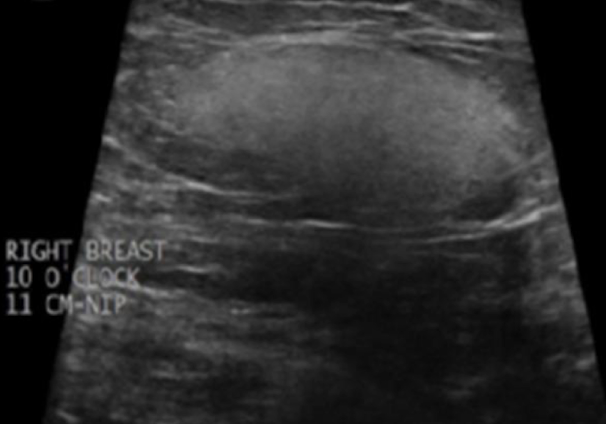

septated cyst$